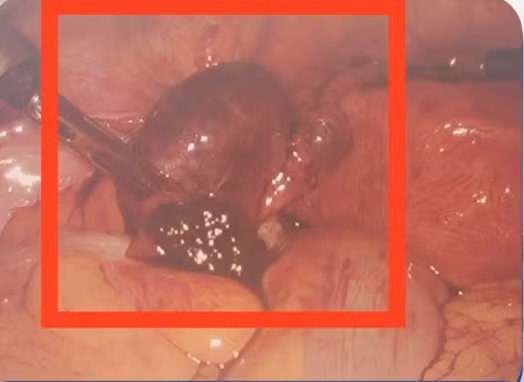

Vỡ khối chửa ngoài tử cung - Ảnh BVCC

Tại đây, qua siêu âm, các bác sĩ nhanh chóng phát hiện bệnh nhân bị vỡ khối chửa ngoài tử cung và lập tức được chuyển phẫu thuật cấp cứu chỉ sau 15 phút nhập viện.

Trong quá trình phẫu thuật, bệnh nhân bị mất nhiều máu. Tuy nhiên, ê kíp đã kịp thời xử trí, cầm máu và bảo toàn tính mạng cho người bệnh. Ca mổ diễn ra thành công. Hiện tại, sức khỏe bệnh nhân đã ổn định, vết mổ khô và đã được xuất viện.